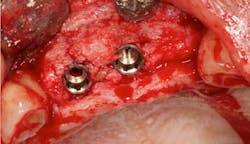

Fig. 2